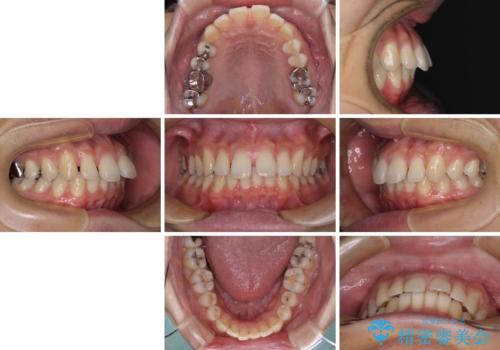

深い咬み合わせと前歯の隙間 ハーフリンガルによる矯正治療

- ハーフリンガル

- 咬み合わせにより上顎正中に隙間ができているとのことで来院された患者様です。

インビザラインは自己管理が煩わしく、表側のワイヤー装置は目立つので避けたいとのことで、上顎だけが裏側装置のハーフリンガルにて矯正治療を行うこととしました。

矯正治療中に結婚式があったそうですが、隙間も改善しており、一部装置を外すことなく挙式できたとのことでした。